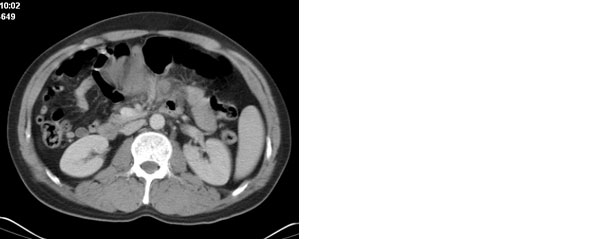

李**,男,46岁,便血1天入院,慢性贫血貌,腹平、软,剑突下压痛,肠鸣音稍活跃,hb大于1g/l,胃镜:慢性浅表性胃炎,b超:1肝内多发性占位 2腹腔内囊性肿块 ,肝内圆形影平扫ct值42.9,动脉期48.6,静脉期58.2,延迟期62.2

影像学表现:1 腹腔前中部、胰腺前方囊实性病灶(个人认为确定有否实性成分存在这是关键,涉及到鉴别诊断,如果是口服阳性造影剂则可明确左侧是不是小肠了),囊性部分囊壁不均,实性部分有强化,与小肠关系较密切,局部小肠受推移;与胰头、胃后壁均有脂肪间隙存在;2 胰腺无异常改变,胰周无渗出;3肝后段包膜下2个小圆形低密度灶,从图像和楼主提供的ct值来看有轻度强化,灶周无片状强化,不似单纯囊肿及肝癌、炎性病变表现;4 腹膜后及腹腔内无淋巴结肿大。

胰腺边界清晰,胰周筋膜不厚,胰周脂肪密度无明显增高;其前方囊实性病灶,边界清晰,增强后实性部分轻度强化;肝内多发边界清晰低密度影,增强后无明显强化(平扫ct值42.9,动脉期48.6,静脉期58.2,延迟期62.2)。

原因:胰头前方,前上腹部巨大囊实性肿物,与小肠关系密切,与胰头及胃壁之间脂肪间隙存在,囊壁不均匀,部分强化,占位效应明显,小肠上段扩张,十二指肠及胃腔内大量食物存留,说明上消化道有部分梗阻。因此,考虑来源于肠道的肿瘤。再结合其病史及肝内改变,这样考虑更有道理。